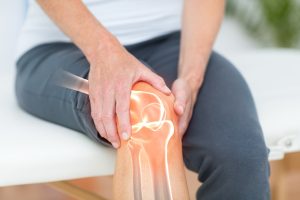

Diz Eklemlerinde Kireçlenme

- Diz eklemi, en sık kireçlenme görülen bölgelerden biridir ve hastaların yaklaşık %35-40’ında bu sorun ortaya çıkar

- Merdiven inip çıkma, oturma-kalkma gibi günlük hareketlerde belirgin zorluk yaşanır

- Yürüme mesafesi kısalır ve eklemde sertlik hissi günlük aktiviteleri kısıtlar

- Özellikle ağırlık taşıma sırasında ağrı yoğunlaşır